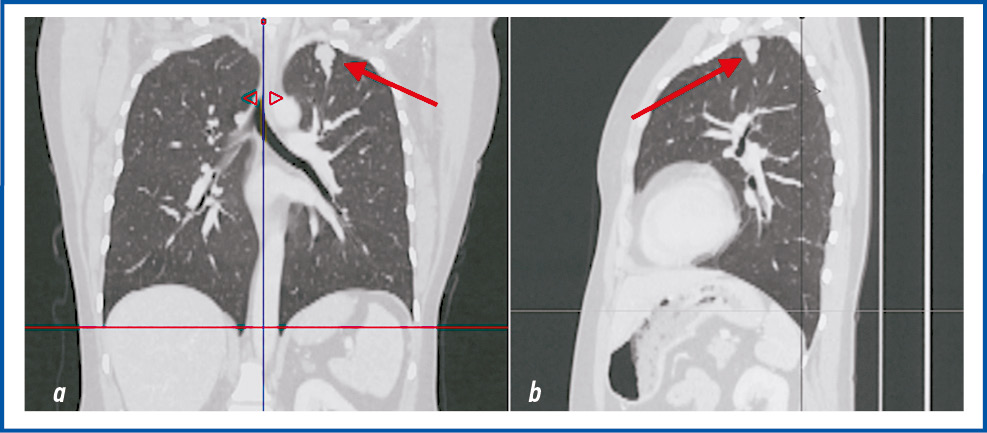

Через 6 лет, в мае 2022 г., пациентка снова обратилась в ГУЗ ОКОД г. Ульяновска, при осмотре – жалобы на боли в животе умеренного характера, слабость. При обследовании по данным мультиспиральной компьютерной томографии (МСКТ и КТ) с контрастным усилением выявлено наличие однородного многоузлового новообразования слева в ЗБП 7×5×8 см с интенсивным накоплением контрастного вещества (рис. 2), множественные образования печени, лимфатические узлы (ЛУ) ворот печени – до 14 мм (рис. 3), 2 образования в легких: 1 – в верхней доле левого легкого, 1 – в нижней доле правого легкого (рис. 4, 5).

Рис. 4. МСКТ. Стрелкой указано новообразование в нижней доле правого легкого.

Fig. 4. MSCT scan. The arrow indicates the neoplasm in the lower lobe of the right lung.

Рис. 5. МСКТ. Стрелкой указано новообразование в верхней доле левого легкого.

Fig. 5. MSCT scan. The arrow indicates the neoplasm in the upper lobe of the left lung.